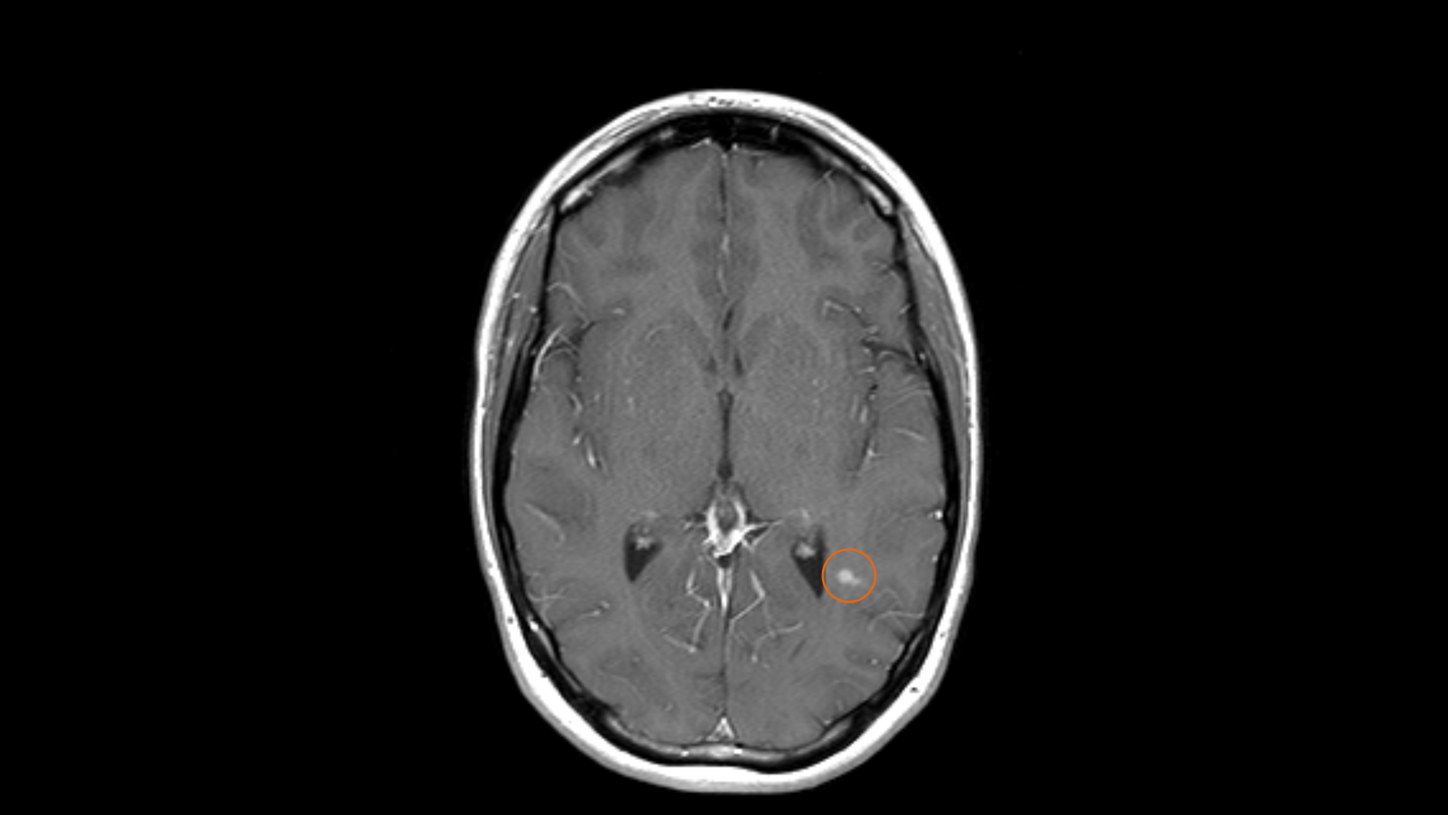

Central Vein Sign (CVS)

T2*-weighted or susceptibility-weighted imaging (SWI) has been shown to be the imaging method of choice to differentiate MS lesions from non-MS lesions. Hyperintensities caused by MS are in the majority of cases focused around a central vein. This vein must be visible in several plane orientations (e.g., axial and coronal) and appears as a dark line or dot, depending on the orientation. It should be central and not along the rims of the WMH. This is the so-called CVS, and it can be visualized by fusing the FLAIR image and the magnitude images of T2* or SWI on MR View&GO or syngo.via.

The 2024 update of the McDonald criteria2 emphasized the role of the CVS for a confirmed diagnosis of MS. Instead of demonstrating DIS and DIT, the diagnosis of MS can now be secured by demonstrating either DIS or DIT plus at least six CVS.